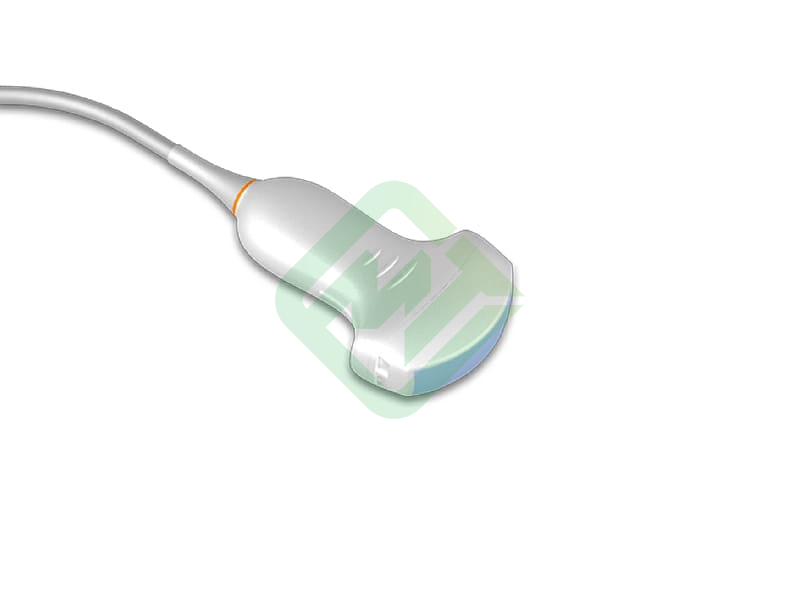

— мультичастотные УЗ-датчики: линейный датчик Edan L742UB, конвексный датчик Edan C352UB, фазированный датчик Edan P5-1b

— конвексным C352UB: частотный диапазон датчика 2–6 МГц, угол обзора 70°, глубина сканирования 320 мм, количество элементов 128

- Датчик конвексный ультразвуковой C352UB — 1 шт.